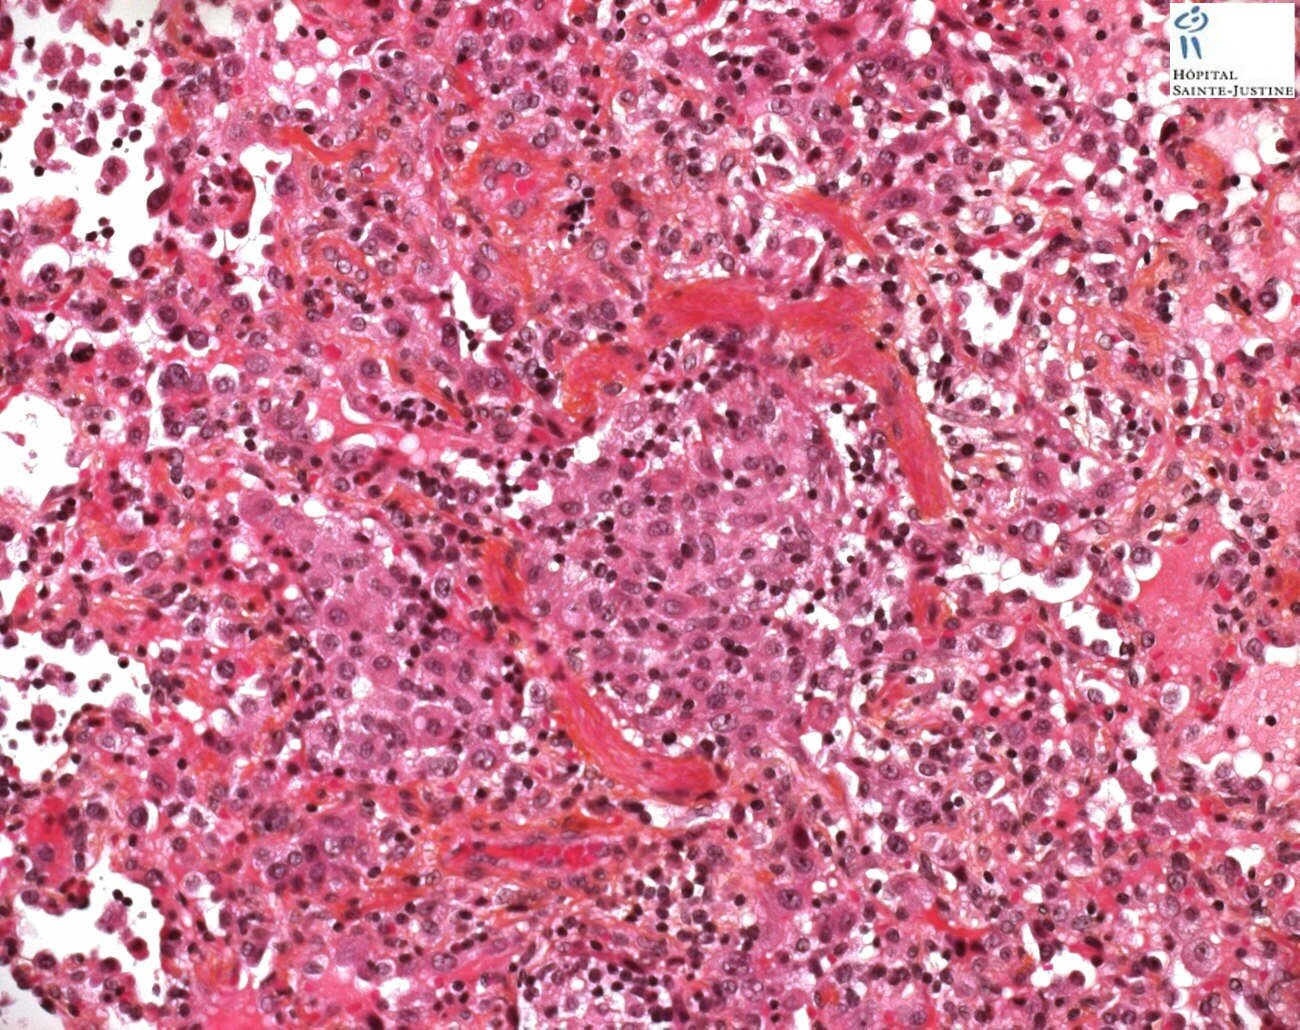

necrotizing bronchiolitis